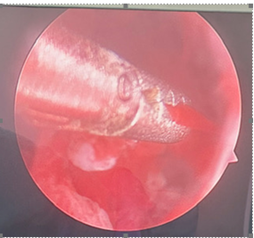

She was given General anesthesia and was put in lithotomy position. Parts of the operative site, the perineal area and vagina were cleaned and painted with betadine and draped. Under aseptic precautions, bladder was emptied. Per vaginal examination was done. Uterus was normal and anteverted. Parts of Hysteroscope were assembled, Vaginoscopy was done followed by hysteroscopy to visualize the cavity of the uterus. The uterine cavity was normal in size and shape, bilateral ostia were normally located. However, no fragmented portion could be traced. While withdrawing the hysteroscopy, a hard structure was felt on the anterior aspect of the lower uterine segment (Figure-2, 3).

Figure 2: Hysteroscopy visualizing the embedded fragment of IUCD.

Figure 3: Hysteroscopy visualizing the embedded fragment of IUCD

As the IUCD was embedded in the myometrium an attempt was made with grasper to bring it into the uterine cavity. Repeated attempts were not enough. Then hysteroscope was withdraw and IUCD hook was used to move the hard part felt and the fragmented bit of IUCD successfully removed (Figure-4).

Malpositions of IUCDs were analysed by Zakin et al (14). According to them, the IUCD which penetrates only into the myometrium of the uterus are termed partial perforation. Such a position as shown in the fig -2 is position type - B. Following a Type –B perforation the IUCD lies entirely within the myometrium so that it cannot be seen either by hysteroscope or laparoscope.